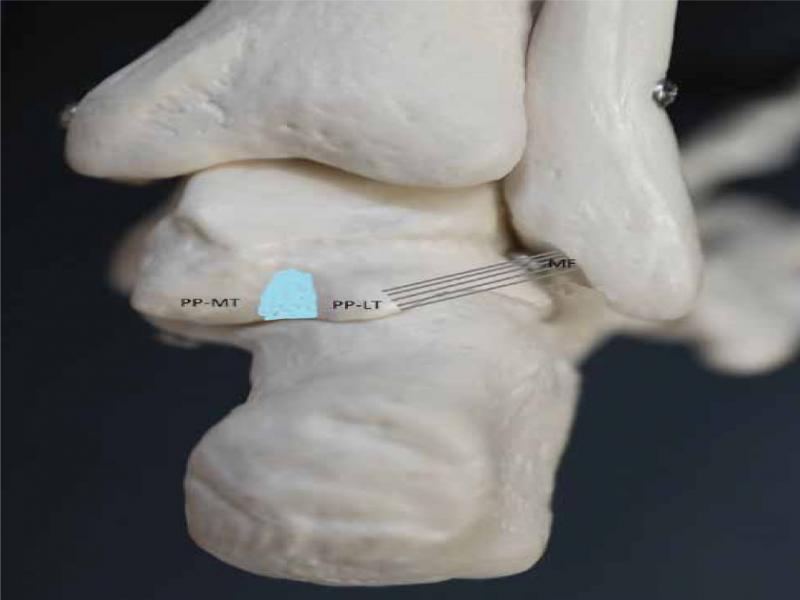

Fig. 1.

Anatomy of the PTFL (PP-LT – lateral tubercle of the posterior process of the talus, PP-MT – medial tubercle of the posterior process of the talus, light blue area – sulcus of the flexor hallucis longus tendon, MF – malleolar fossa of the lateral malleolus, grey lines – typical course of the posterior talofibular ligament)

In the anatomic structure, the main focus should be placed on the posterior process of the talus, which has two tubercles – medial and lateral. Between these tubercles, there is a notch, in which the tendon of the flexor hallucis longus runs (Fig. 1).

The posterior talofibular ligament connects the malleolar fossa, located on the medial surface of the lateral malleolus, with the lateral tubercle of the posterior process of the talus(1,2). In order to properly visualize PTFL, it is necessary to identify the bony structures properly, especially the lateral tubercle of the posterior process of the talus. It should be noted that ligaments, in the majority of cases, form a reinforcement for the joint capsule and as they are placed deeply, they form a tissue layer close to the bone. The structure of echogenicity and the structure typical for a ligament placed deeply and connecting the fibula with the lateral tubercle of the posterior process of the talus can be easily identified as PTFL (Fig. 2A, Fig. 3) To evaluate this ligament, we suggest to place a patient in a prone position and bend the ankle to 90 degrees in the limb undergoing examination (with feet resting on the toes – Fig. 2B), although experienced diagnosticians should not encounter problems with visualization of the ligament with a patient in the supine position with a limb bend in the knee and with the foot resting on the ground.